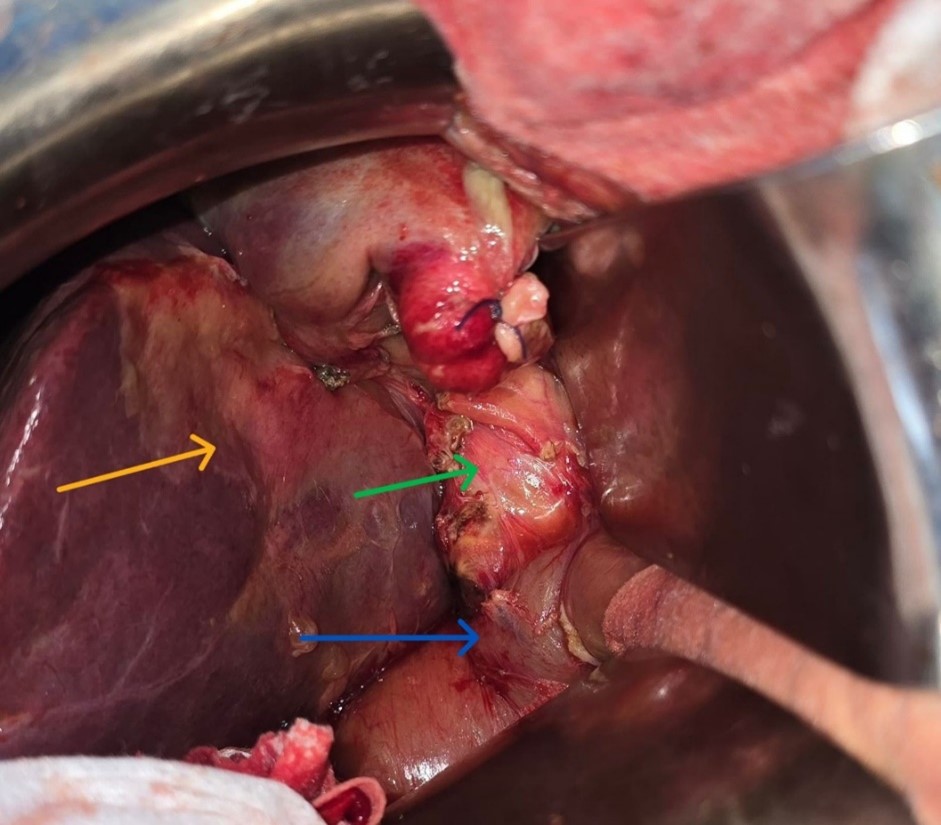

Given the clinical presentation suggestive of localized biliary peritonitis, the patient was taken emergently to the operating room. Abdominal access was achieved through a right subcostal incision. Surgical exploration revealed dense colohepatic, omentohepatic, and gastrohepatic adhesions. Laborious adhesiolysis exposed a collection of approximately 200 mL of infected bile, which was aspirated and evacuated. The common bile duct was markedly dilated to 3 cm and contained two large stones, with a thickened and inflamed wall. The gallbladder could not be clearly identified due to advanced inflammatory changes in the subhepatic region, making further dissection hazardous.

Figure 2: Intraoperative view demonstrating absence of the gallbladder (gallbladder fossa, yellow arrow), a dilated common bile duct (green arrow), and the duodenum (blue arrow).